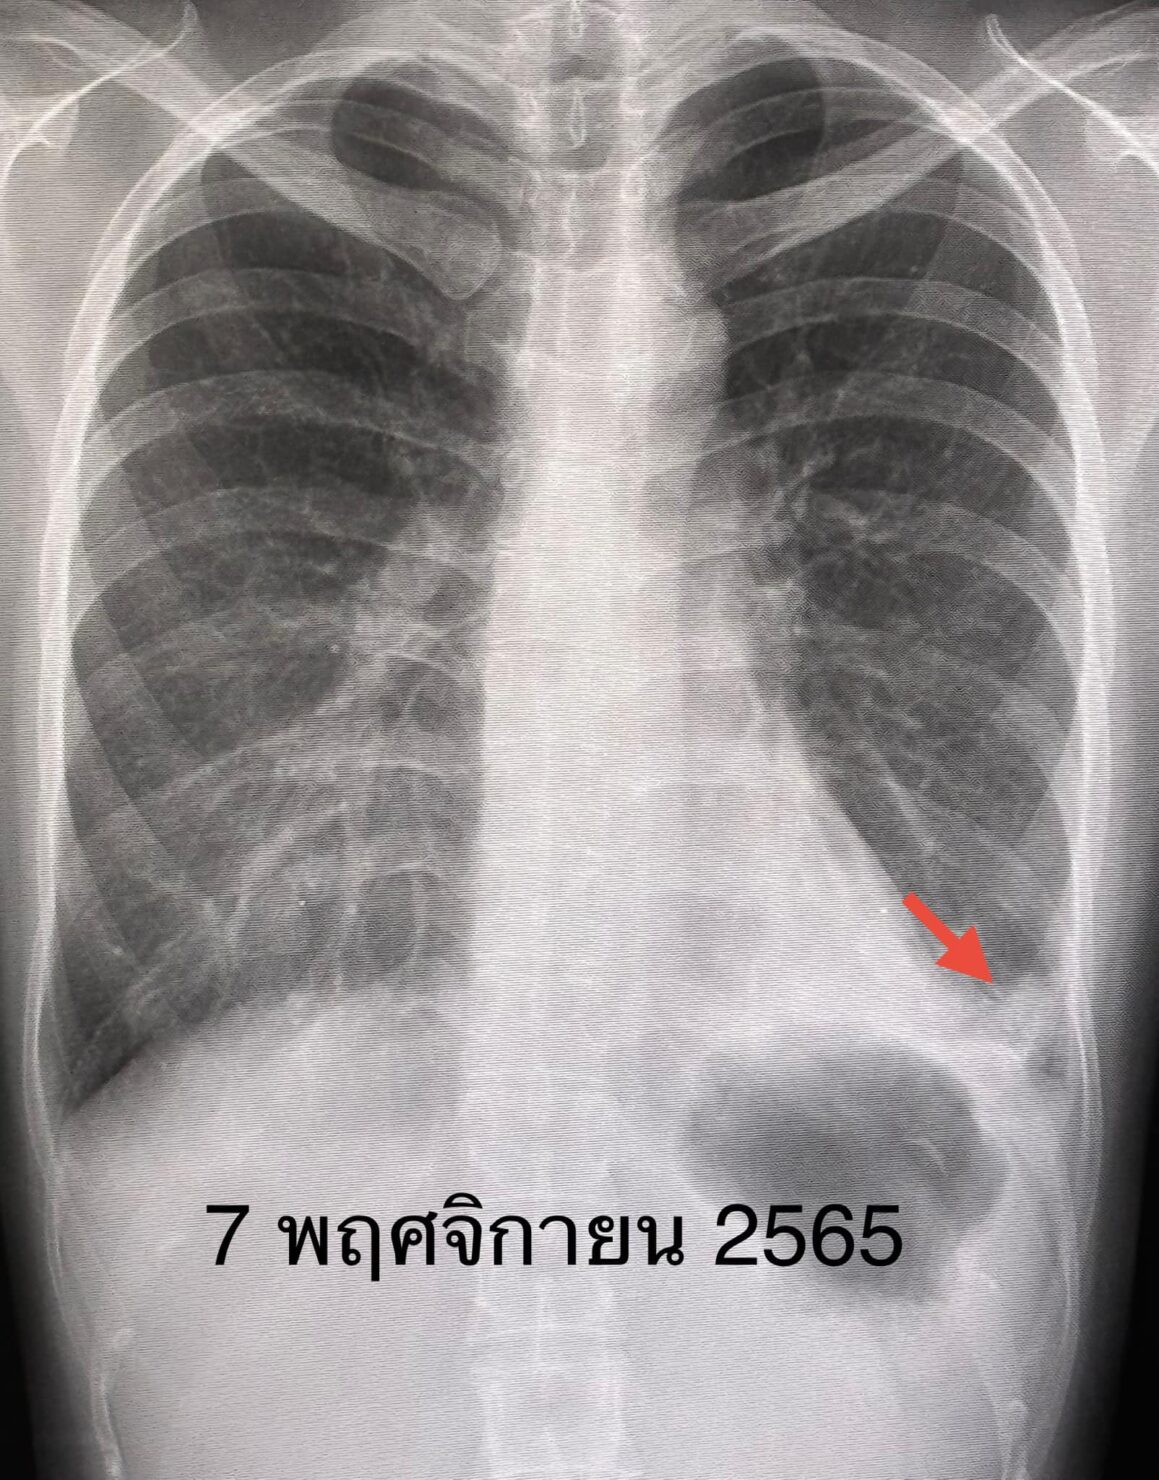

เอกซเรย์ปอดมีฝ้าขาวที่ปอดซ้ายด้านล่าง(ดูรูป ) คอมพิวเตอร์ปอดเห็นฝ้าขาวที่ปอดซ้ายด้านล่าง(ดูรูป) ทำสมรรถภาพปอดพบความจุของปอดลดลง เจาะเลือดค่าอักเสบของเลือดสูงเล็กน้อย ESR 31, hs-CRP 11.2, ANA positive 1:1280 Anti-MDA5 positive 3+, ค่าอักเสบของกล้ามเนื้อ CPK ปกติ 62

ผู้ป่วยได้วัคซีนไฟเซอร์เข็มที่ 3 เดือน ม.ค. 2566 เพราะกลัวว่าหากติดไวรัสโควิด-19 อาจป่วยรุนแรง เนื่องจากกำลังกินยากดภูมิคุ้มกัน ปรากฏว่า 5 วันหลังฉีดวัคซีนไฟเซอร์ ผื่นที่หน้า ข้อมือ ข้อศอก คอ หลังส่วนบน กลับมาเป็นมากขึ้น ไอ เหนื่อยเวลาออกกำลังกาย เอกซเรย์ปอดและคอมพิวเตอร์ปอดเห็นฝ้าขาวเพิ่มขึ้นที่ปอดด้านล่างทั้ง 2 ข้าง(ดูรูป)